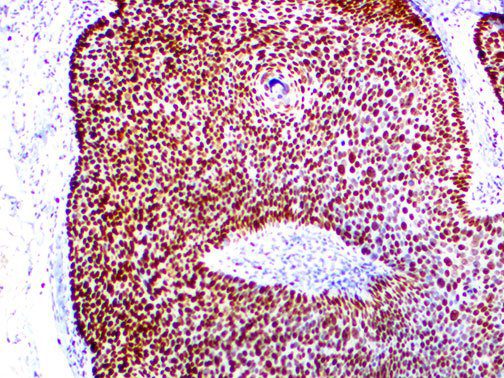

The first cytokines released are interleukin 1β (IL-1β) and tumor necrosis factor-α (TNF-α), which attract a variety of circulating white blood cells (WBCs) to the infection site, including neutrophils, monocytes, macrophages, and natural killer (NK) cells. This response, along with the antipathogenic chemicals released by these cells (i.e., complement), comprise the innate immune response. These cells directly attack the invading pathogen and also release additional cytokines, chief among them interleukin-1 and 6 (IL-6). IL-6 is essential for invoking the adaptive immune response, which calls T-cells, B-cells, and T helper (Th) cells to the infection site. IL-6 also stimulates further recruitment, proliferation and activation of macrophages.

It is the ICU physician who is most likely to witness one of the deadliest manifestations of the abnormal immunological response, the cytokine storm syndrome (CSS). This response is also referred to by some as the cytokine release syndrome (CRS). CSS is characterized by continuous activation and expansion of macrophage and lymphocyte populations, which secrete large amounts of cytokines, causing the cytokine storm. This massive cytokine release is akin to hemophagocytic lymphohistiocytosis (HLH) disease, a syndrome characterized by initial unchecked and persistent activation of cytotoxic T lymphocytes and NK cells.